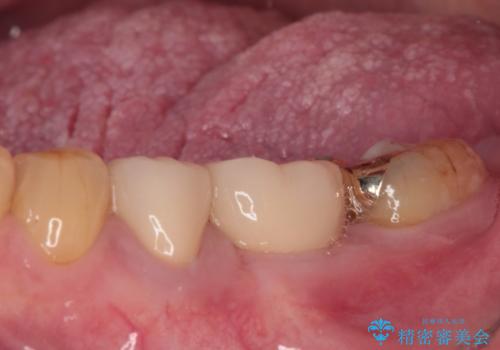

改めて診療を行ったところ、歯根破折が認められ、抜歯後にインプラント治療を行うこととしました。

下顎大臼歯の抜歯決断までに時間がかかったため、治療期間はやや長くなりましたが、安定した咬み合わせとなり、痛みもなく安心して噛めるようになりました。